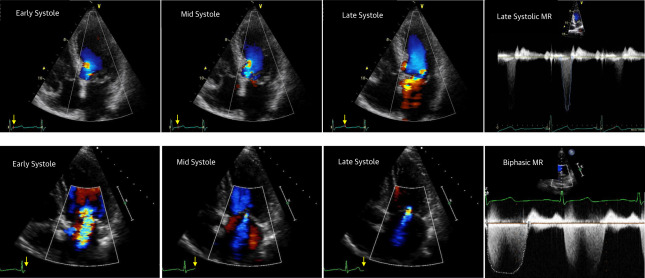

MR的总体反流量应该是时间每一刻反流量的时间积分,反流总量除了和瞬间反流量有关,也和持续时间有关。因此,MR在同一心脏周期的收缩期内也是动态变化的(图9),不能靠某一时刻单帧的反流量去评估反流量。非全收缩期MR常见,单帧的面积测量(二维思维)会高估MR。

图9  MR的严重程度在心动周期内也是动态的

之前,笔者阅读国外文献关于MitraClip解剖入选标准,要求对于FMR的病人,前后瓣尖端之间接合长度要大于2mm。那么问题来了,既然前后瓣叶都接合重叠了,那怎么会出现反流?这个问题解释必须从MR时空滞后角度去分析。 (图10-11),这些患者,由于乳头肌部位心脏收缩减弱,瓣膜被腱索牵拉而不能闭合,出现了收缩早中期的瓣膜闭合延迟而出现MR,而到了收缩晚期,心脏收缩幅度加大,向瓣环靠拢,腱索没受到牵拉而出现了瓣膜闭合和接合。所以,这些患者的MR并非全收缩期,只存在于收缩早中期。左束支传导阻滞患者出现MR主要叶是该机制,因此,通过纠正心脏收缩顺序可以治疗MR。同样,我们中心近期在《European Heart Journal - Case Reports》[3]报道了一组舒张期MR的有趣病例,这些病例甚至二尖瓣的解剖完全正常(图12)。其发生机制也是心脏收缩的时间顺序发生紊乱,导致心室和心房之间的压差逆转或者腱索被提牵拉限制,从而导致MR。